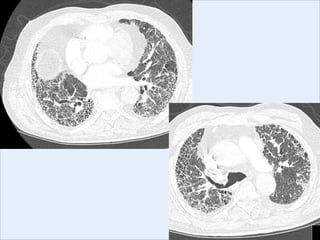

FEV1 2.25L (9% predicted) FVC 2.74L (65% predicted) ratio 0.82

Total lung volume 79% predicted, TLCO 48% predicted.

CXR

CT

Imaging: thickened interlobular septa, ground glass

infiltration, and honeycombing in a sub-pleural and

basal distribution